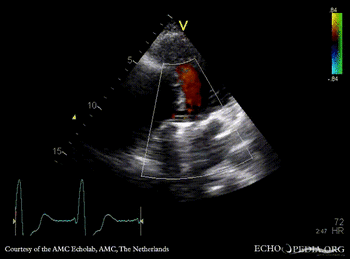

PLAX: mitral valve prosthesis and aortic valve prosthesis PLAX with Color Doppler